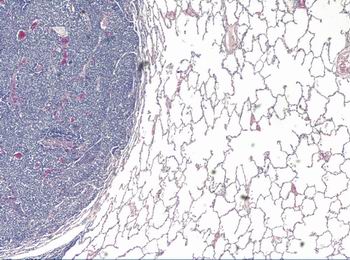

Figura 15 - <div style=fiogf49gjkf0dDetalle a mayor aumento de la imagen anterior (HE 200x).">

Figura 15 -

fiogf49gjkf0d

Detalle a mayor aumento de la imagen anterior (HE 200x).

2.- Pulmones: tromboembolismo neoplásico en arteria pulmonar izquierda, que la obstruye totalmente (Figuras 12 y 13 ). Implantes neoplásicos de similares características a las descritas en región lumbosacra, difusamente distribuidos en lóbulo superior izquierdo y los tres derechos (Figuras 14 y 15). En lóbulo inferior izquierdo, neumonía en resolución, con ocupación de la luz alveolar por células mononucleadas, abundantes macrófagos y edema.